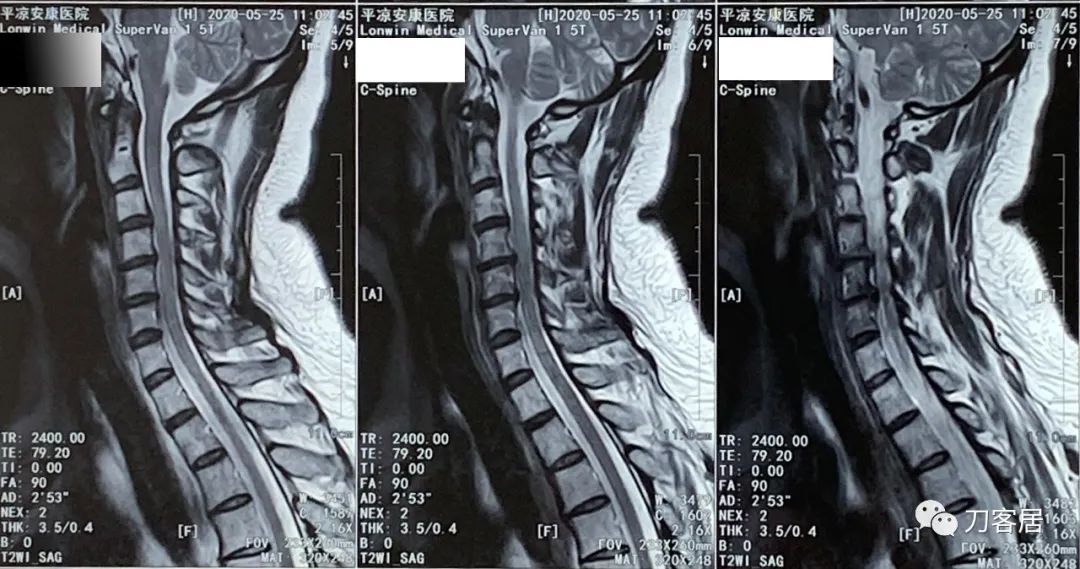

患者回家后又到当地医院做颈椎MRI检查。

图13. 20200525平凉安康医院颈椎MRI01

图14. 20200525平凉安康医院颈椎MRI02

图15. 20200525平凉安康医院颈椎MRI03

图16. 20200525平凉安康医院颈椎MRI04

2020年5月25日做的颈椎MRI并没有新的发现,仍然是颈3-6椎间盘变性及轻度突出,颈6-7椎间盘变性并膨出,颈椎生理曲度不稳,局部反弓。